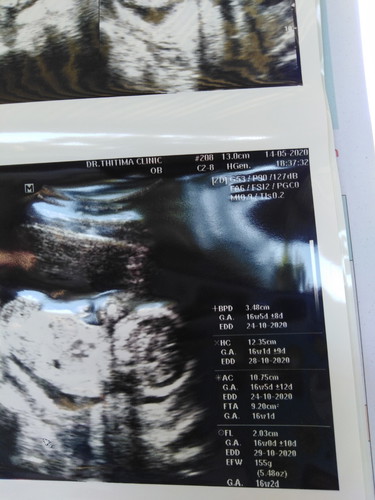

ตอนนี้ท้องได้16wค่ะ ไม่ค่อยเข้าใจกับค่าต่างๆในใบซาวน์ คุณหมอไม่เคยพูดให้ฟังเลย